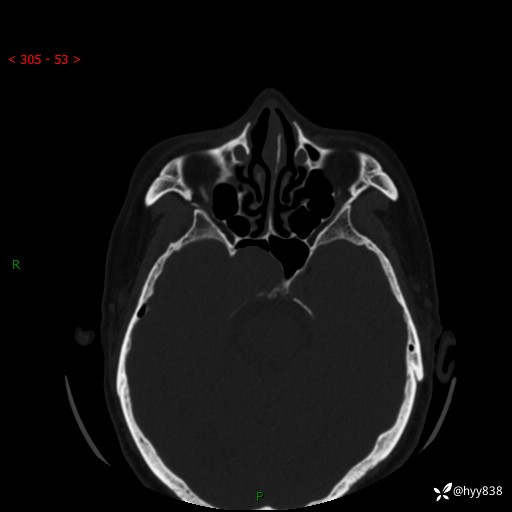

蝶鞍CT平扫